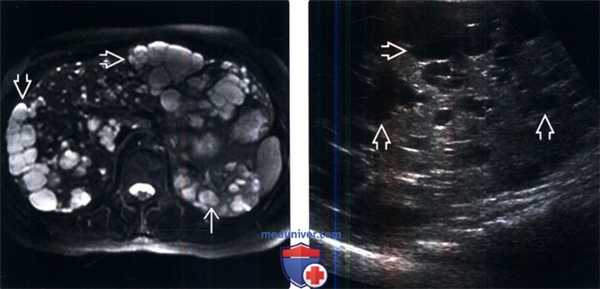

Рисунок 1,2, Т2-ВИ в корональной и аксиальной проекциях, поликистоз почек: в области обеих почек определяются множественные сгруппированные, гетерогенные по МР-сигналам дополнительные образования, с четкими, ровными контурами, в единичных с уровнем жидкости, а также с геморрагическим компонентом, неизмененная паренхима почек визуализируется в виде небольших участков.

Рисунок 3,4, Т2-ВИ в аксиальной проекциях, поликистоз почек: в области обеих почек определяются множественные сгруппированные кистозные образования, в области правой почки большим размером, вероятно с высокобелковым содержимым.